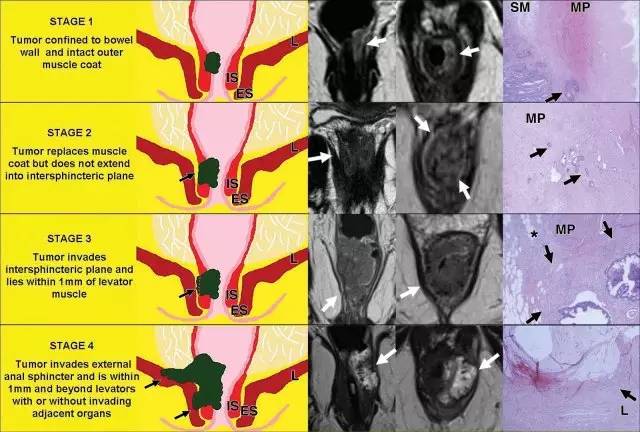

口诀 3:「A」

肛门复合体 - 括约肌和直肠肌

肛管直肠结合部,直肠固有肌层变化:1. 环形肌变厚形成内括约肌。2. 外括约肌复合体由肛提肌最下部,耻骨直肠肌和外括约肌组成。3. 低位肛管中两个括约肌形成明显的括约肌间隙。

低直肠肿瘤与阳性切缘率较高,局部复发率高,存活率差相关。这主要是由于解剖学考虑以及直肠系膜在此水平下降的事实。

有学者提出了一种低直肠肿瘤 T 分期。这种分期是基于冠状和轴向 T2 加权图像。

对于低直肠肿瘤,可以根据肿瘤分期进行三种不同的手术方式。